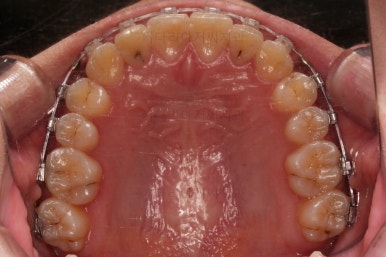

사용한 장치 : 자가결찰 세라믹(엠파워 클리어, Empower clear) + 미니스크류

입 안을 보면 밑에 치열이나 다른 부분은 비교적 양호한데 유달리 윗니 송곳니만 위치가 좋지 못하네요.

이번에 사용한 장치는 엠파워 클리어라고 하는 자가결찰 세라믹 장치인데요.

철사를 잡아주는 뚜껑이 브라켓에 달려있어 스스로(자가) 철사를 잡을 수 있는(결찰) 장치라는 뜻인데요. 대표적으로는 클리피씨라고 하는 장치가 있습니다. 클리피는 일본장치, 엠파워는 미국장치라는 차이점만 있고 큰 틀에선느 동일한 장치라고 볼 수 있습니다.

충치가 곳곳에 보이는데요.

성인들은 충치가 멈춰있는 정지우식일 가능성도 있으며 크기가 현재 크지 않고 향후 변화되지 않는다면 그대로 두기도 합니다.

이번 환자분도 교정치료에 방해되는 부분이나 급해보이는 추료만 우선 진행하고 교정 중에 충치가 커지는지 증상이 생기는지 관찰해 보기로 했습니다.

연산동교정치과 교정장치 부착 직후의 모습입니다.